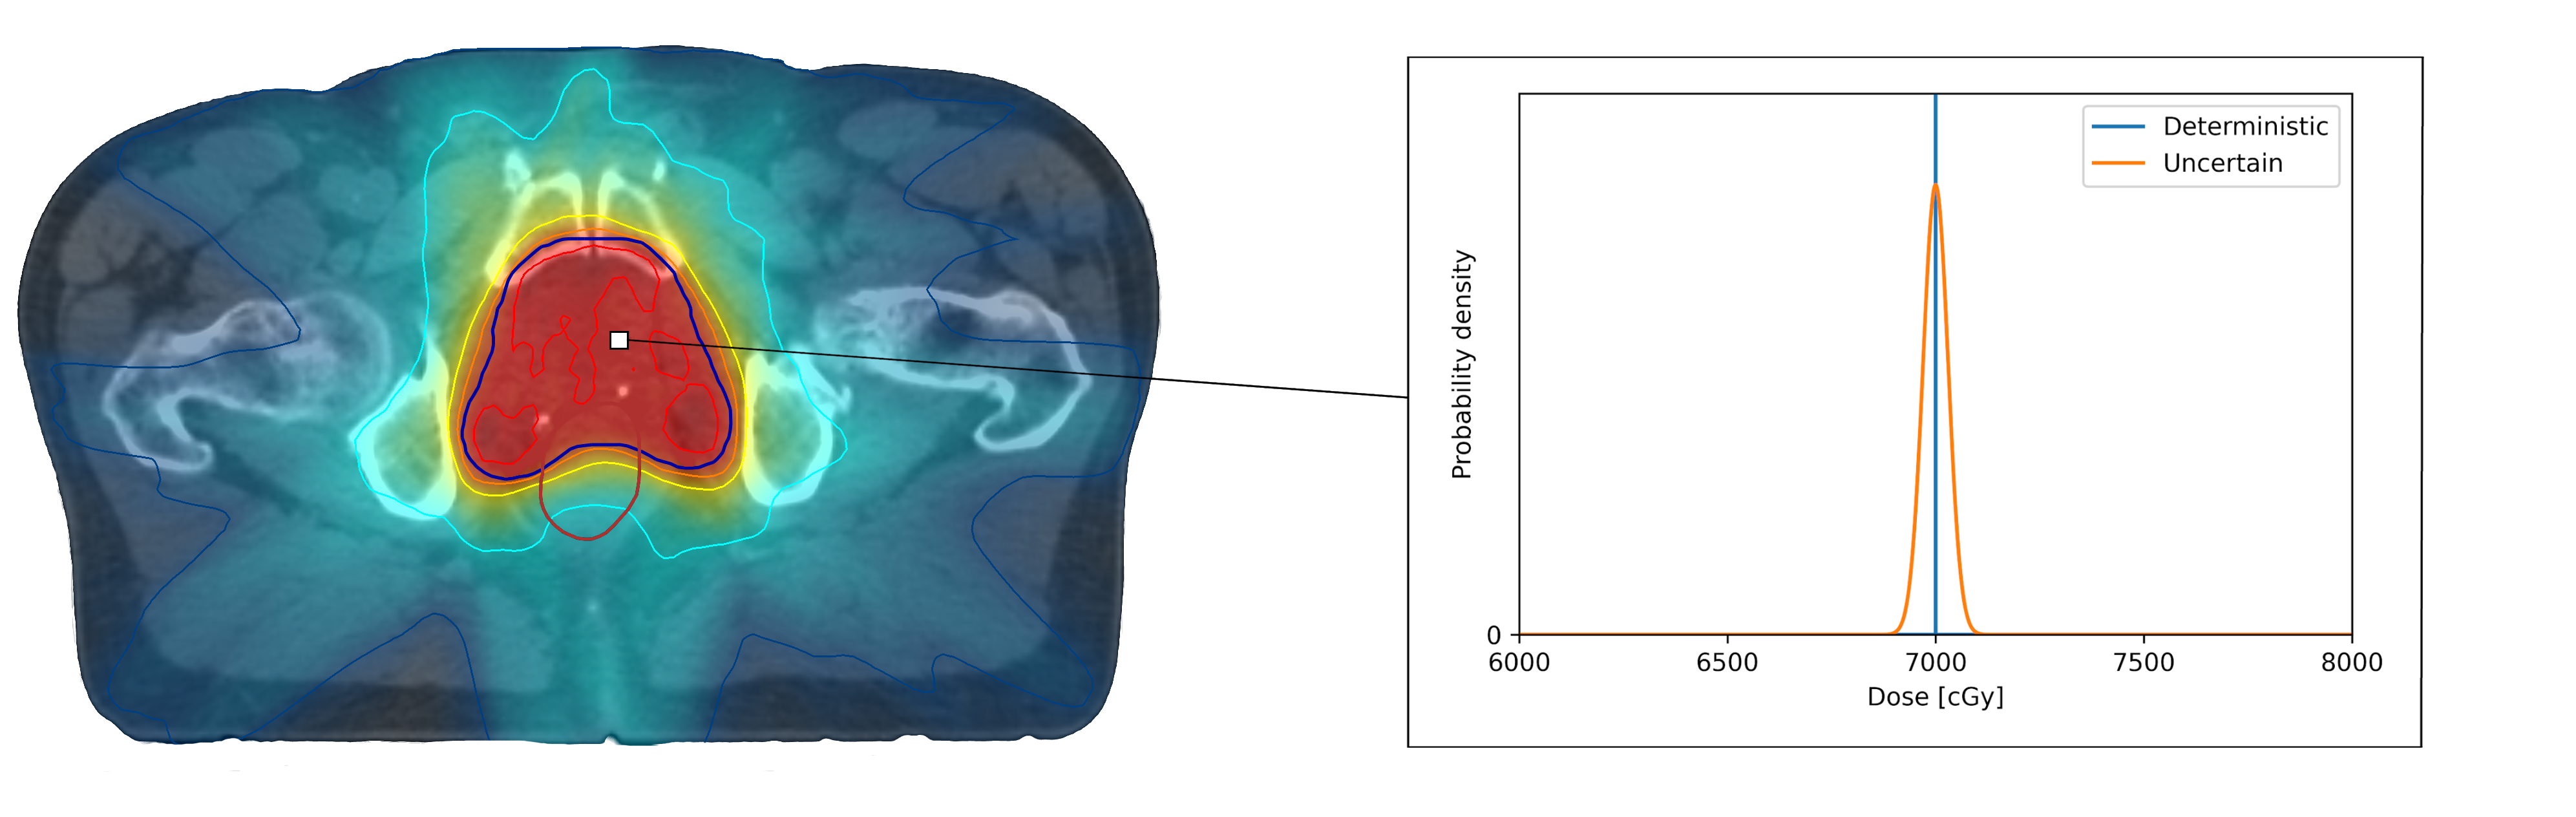

In order to reflect a range of possible predictions with an ML model, its output must comprise more than a deterministic output, such as a single dose value per voxel. A more informative output would instead be a probability distribution per voxel, reflecting the range of possible outcomes of dose values and their respective likelihoods given the planning standards learned from the training data. In figure 1, an example of such a probability distribution for a voxel in the target area is depicted.

Refer to caption

Figure 1: Visualization of a probability distribution of dose versus a deterministic dose for a voxel in the target area.